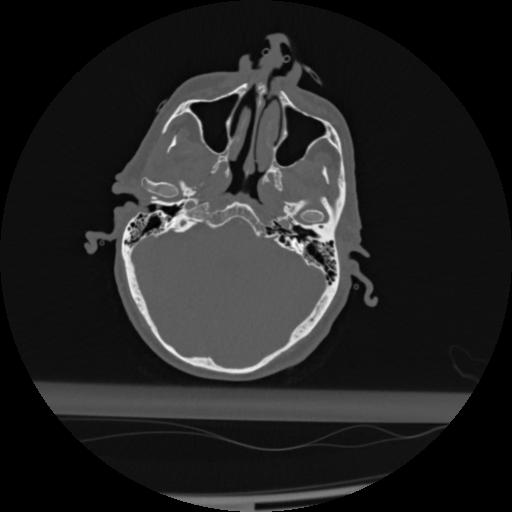

22 ANGIO,CE,Vol,0.5,ANGIO,,